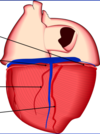

Identify the branches!